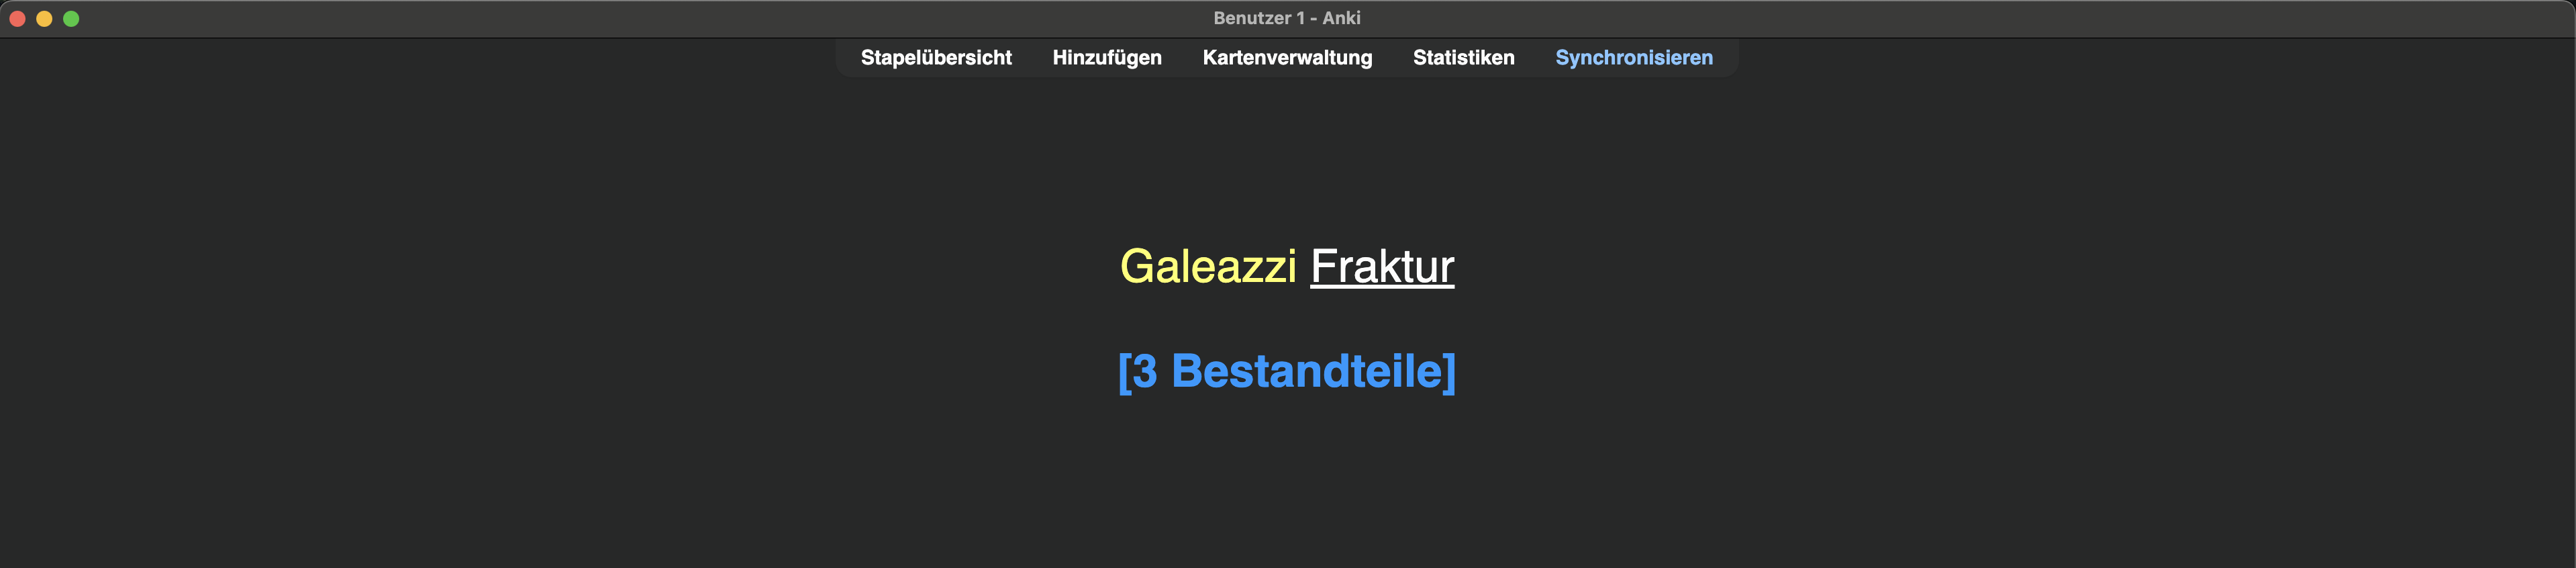

- Defi.: Bestandteile eines medizinischen Terminus – z. B. Galeazzi-Fraktur

Die abzurufende Information „3 Bestandteile“ kann auch in Blau in der Klammer vor Beantwortung der Frage dargestellt werden. Dazu ::3 Bestandteile hinter die Antwort einfügen (der :: erlaubt diese Funktion). Das ist eine Präferenzfrage; ich mache es gerne so:

So sieht die Karte während des Lernens aus:

Sollte sich eine Information bildlich darstellen lassen, nutze das unbedingt! Also auch eine Abbildung der Galeazzi-Fraktur und du musst den Namen nennen. Wenn mir eine Frage nur ein Bild zeigt, ist es für mich eindeutig, dass ich das Bild benennen soll, daher nutze ich diese Struktur: {{c1::Galeazzi Fraktur::Bild}}